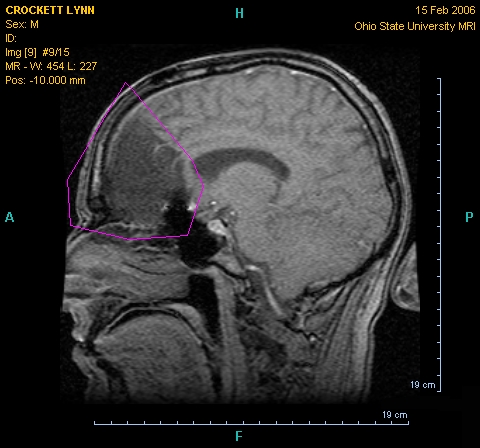

4) Invasive tumours are deadlier than external tumours

‘Tumours like this grow into the brain instead of displacing it, the tumour cells pushing into the brain’s soft substance, weaving their way between the nerve fibres and the brain cells of grey matter. The brain can go on working for a while even though the tumour cells are boring into it like deathwatch beetles in a timber building, but eventually, just as the building must collapse, so must the brain.’

One silver lining to Marsh’s book is that you learn that some famously intimidating tumours can be benign. The huge golf-ball tumour that appears on brain scans in TV serials and films is often not the short straw in the realm of brain tumours. These tumours are mostly external to the brain which essentially sit on it and decompress it – they displace the brain, which can cause death from excess pressure. These however can be removed and the patient can make a full recovery. The tumour to fear is one that will appear on a scan like a dark smudge. This is invasive and may alter everything from your personality to your vital senses before killing you. These tumours are therefore much harder to treat, and removal involves careful manoeuvring around critical brain tissue. Marsh’s accounts of these surgeries are often harrowing.